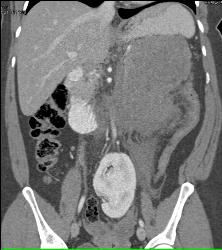

GIST Tumor